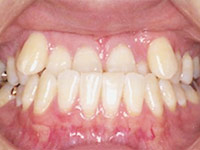

正常な歯の状態右のような歯の状態が正常な歯並び・噛み合わせです。お子さんの今の歯の状態と見比べた時、どの写真に一番近いでしょうか。下のような写真とまではいかなくても、少しでも気になるところがあれば注意が必要です。

正常な歯の状態